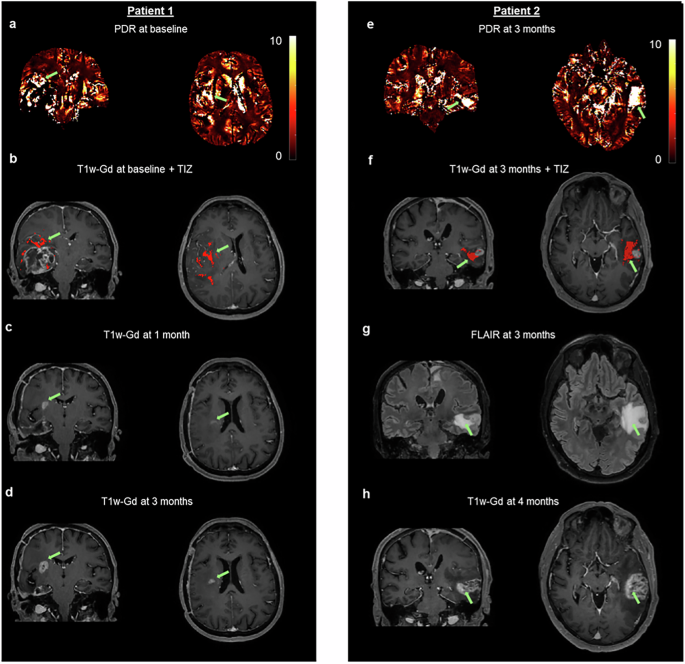

Spatial distribution of PDR in edema suggests tumor infiltration

To demonstrate the potential of PDR for detecting tumor infiltration, in Fig. 4, we report two patients as observational cases. For both patients, the evolution of the disease happened at a different location with respect to the one observed at the initial diagnosis. For one patient (Fig. 4a–d), PDR at baseline (Fig. 4a) shows specific areas in edema with very high values from which the “TIZ” is delineated. On the T1w-Gd of the same session, the location of the segmented “TIZ” (Fig. 4b, red area) is above the contrast-enhancing tissue of the glioblastoma. One month later, at the location corresponding to one of those indicated by the “TIZ,” contrast-enhancement appears on the T1w-Gd (Fig. 4c). Three months after surgery, the tumor progression is still ongoing at the same location (Fig. 4d). Note that there were other scattered “TIZ” voxels that did not lead to contrast-enhancement at one month nor at three months post-surgery. As the patient died shortly afterward, we do not have later time points to assess whether these “TIZ” voxels would lead to later enhancement. For another patient (Fig. 4e–h), PDR at three months shows a striking hyperintensity in areas of edema (Fig. 4e), and the corresponding “TIZ” is overlaid on the T1w-Gd (Fig. 4f, red area). T1w-Gd shows no contrast enhancement in the “TIZ,” while FLAIR shows that the “TIZ” is within the edema tissue (Fig. 4g). One month later, contrast enhancement can be observed at the location indicated by the “TIZ” at the three-month MRI acquisition. The patient underwent a second surgery due to the suspicion of tumor localization. Glioblastoma was confirmed at pathology. Together, these observations suggest the potential of the PDR to track tumor infiltration through edema.

For one patient, PDR at baseline acquisition (a) from which the “TIZ” (red area) is segmented in edema, and it is overlaid on the T1w-Gd (b). One month after surgery, on the T1w-Gd (c), tumor enhancement appears at the same location indicated by the “TIZ” at baseline. Three months after surgery on the T1w-Gd (d), the tumor is growing at the same location. For another patient, PDR at three months after surgery suggests tumor infiltration (e) in an area of no contrast-enhancement on T1w-Gd at the location suggested by the “TIZ” (red area) (f). The corresponding location appears homogeneous on FLAIR (g). Four months after surgery on T1w-Gd, the tumor has invaded the location pointed by the “TIZ” (h). Green arrows indicate the location of tumor infiltration suggested by PDR. Images presented here are co-registered to the PDR image space of the corresponding patient.